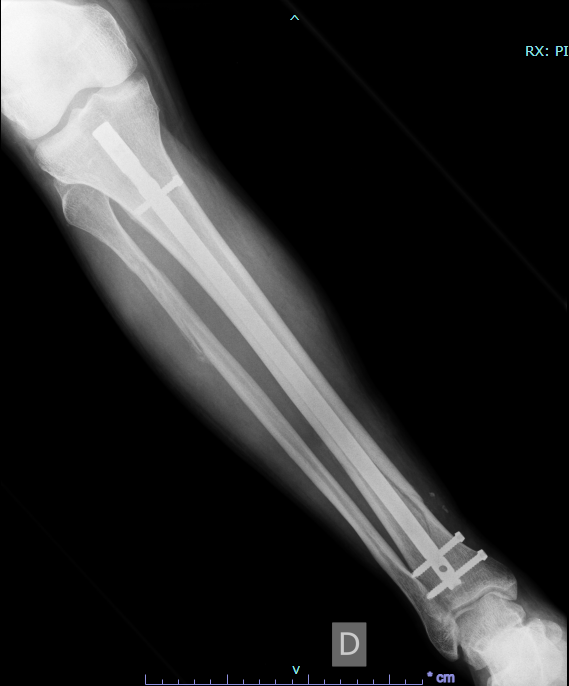

Rotura Tibia Y Peroné Operación Con Clavo Intramedular, , , , , , , 0, Tratamiento de fractura de tibia y perone en niños y adultos, www.fisioterapiaparatodos.com, 709 x 616, jpeg, WebFractura abierta de tibia y peroné. Se trata de una fractura en la que la piel está perforada y los huesos son visibles a través de la herida, y requiere una intervención. WebLa utilización de un clavo intramedular en caso de fracturas de tibia y peroné es para ayudar a que los huesos fracturas tengan un optimo proceso de consolidación, y para su retiro., 20, rotura-tibia-y-perone-operacion-con-clavo-intramedular, Novedades y Muebles WebFractura abierta de tibia y peroné. Se trata de una fractura en la que la piel está perforada y los huesos son visibles a través de la herida, y requiere una intervención. WebLa utilización de un clavo intramedular en caso de fracturas de tibia y peroné es para ayudar a que los huesos fracturas tengan un optimo proceso de consolidación, y para su retiro.

WebPues mira, yo llevo casi 9 meses de operado (tengo 2 clavos intramedulares de titanio, 8 tornilllos, tuve fractura de tibia, perone, femur, empeine y un dedo del pie. WebSi se utiliza un “clavo intramedular” para fijar la tibia rota (es el tipo de cirugía más común para una pierna rota), las personas suelen poder caminar con la pierna.

WebYo con rotura de tibia y peroné, me metieron un hierro intramedular en la Tibia con tornillos en la rodilla y abajo llegando al tobillo. Tarde casi 3 años en quitarlos y. WebProtocolo de rehabilitación de fracturas de tibia pdf. Se incluyeron 88 pacientes con 90 fracturas de tibia. Se utilizaron los siguientes criterios de inclusión: (1) pacientes adultos. WebLa fractura, como habíamos dicho más arriba, puede producirse en la tibia, en el peroné o en ambos huesos, y puede ser causada por un golpe, una caída, por un mecanismo de. WebAhora el turno de la tibia, en donde abren en la rodilla y meten el clavo intramedular, acomodandolo y fijandolo con sus tornillos. El perone, ya estaba. Webprotocolo de fisioterapia para clavos intramedulares en la tibia. ResumenEl enclavado intramedular con bloqueo estático y fresado sigue siendo el tratamiento estándar para. WebMe operaron y pusieron un clavo STRIKER 2 intramedular de tibia cpn dos tornillos sujetándolo, uno en tobillo y otro abajo de la rodilo; además de dos.

WebPARA LA FRACTURA DE LA TIBIA CON CLAVO INTRAMEDULAR ACTIVIDAD NO ASPOYE PESO en la pierna operada hasta que se lo permita el Dr. Gilmer. Por favor. WebUn clavo intramedular plantea la interferencia de la circulación intramedular y aunque la llegada de los vasos es fundamental en la reparación de las fracturas, los dos sistemas. WebMe fracturé tibia y peroné con desplazamientos hace 25 días. Durante los primeros 7 días llevé un yeso, después pasé por intervención donde se colocaron fijadores externos y a.

WebMe operaron y pusieron un clavo STRIKER 2 intramedular de tibia cpn dos tornillos sujetándolo, uno en tobillo y otro abajo de la rodilo; además de dos. WebHace 4 meses tuve fractura abierta de tibia y peroné, con operación para colocar clavo en la tibia, el peroné lo han dejado libre. Comencé con la fisioterapia al mes de operada para.